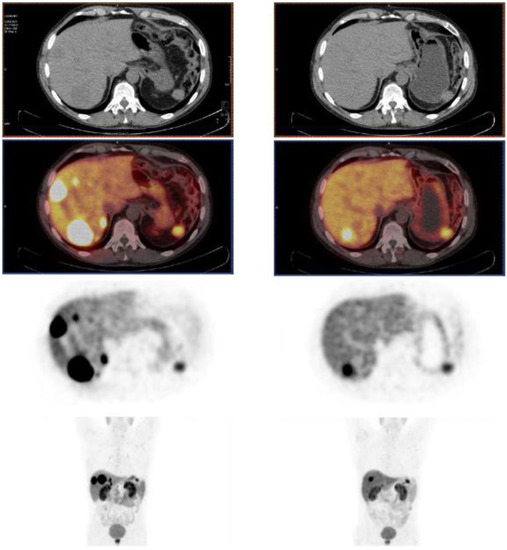

- Zhang, J.; Kulkarni, H.R.; Baum, R.P. Peptide Receptor Radionuclide Therapy Using 225Ac-DOTATOC Achieves Partial Remission in a Patient with Progressive Neuroendocrine Liver Metastases after Repeated β-Emitter Peptide Receptor Radionuclide Therapy. Clin. Nucl. Med. 2020, 45, 241–243. [Google Scholar] [CrossRef]

- Alan Selçuk, N.; Demirci, E.; Ocak, M.; Toklu, T.; Ergen, S.; Kabasakal, L. Almost Complete Response with a Single Administration 225Ac-DOTATATE in a Patient with a Metastatic Neuroendocrine Tumor of Unknown Primary. Mirt 2022, 31, 139–141. [Google Scholar] [CrossRef]

- Satapathy, S.; Sood, A.; Das, C.K.; Kavanal, A.J.; Mittal, B.R. Alpha Before Beta: Exceptional Response to First-Line 225Ac-DOTATATE in a Patient of Metastatic Neuroendocrine Tumor with Extensive Skeletal Involvement. Clin. Nucl. Med. 2022, 47, e156–e157. [Google Scholar] [CrossRef] [PubMed]

- Budlewski, T.; Król, Z.J.; Bruchertseifer, F.; Majkowska-Pilip, A.; Morgenstern, A.; Wierzba, W. Innovative Radioisotope Therapy for Patients with Neuroendocrine Tumors Using an Alpha (225Ac) Emitter Labeled Somatostatin Analog: Octreotate. A Promising New Treatment for Advanced, Progressive Neuroendocrine Neoplasms. Pol. Arch. Intern. Med. 2022, 132, 16275. [Google Scholar] [CrossRef] [PubMed]